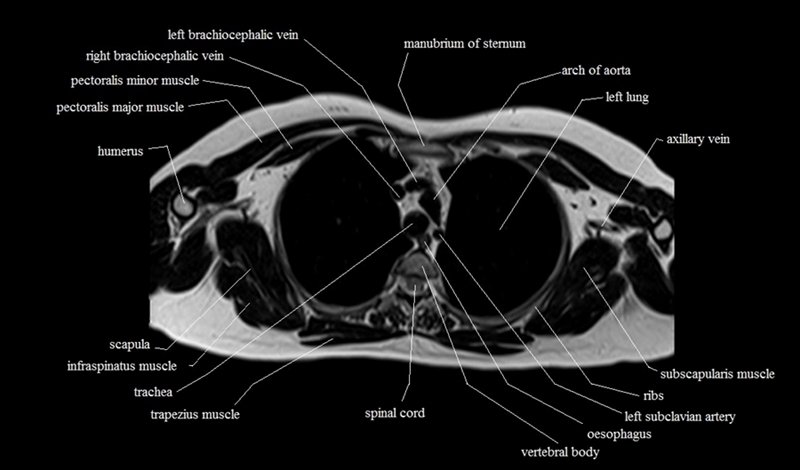

MRI Axial Cross Sectional Anatomy of Chest

This MRI chest (thorax) axial cross sectional anatomy tool is absolutely free to use. Use the mouse scroll wheel to move the images up and down, or alternatively, use the tiny arrows (→) on both sides of the image to navigate through the images. For a more detailed view, double-click the image to view it in full screen, and use the menu in the top right-hand corner to view individual slides or play them in a loop.